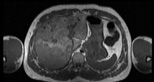

Visible Human male: Sectio transversalis 1525

CT

NMR

Pd                          / T2 \                         T1